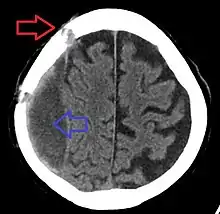

![]() | |

| Subdural hematoma as marked by the arrow with significant midline shift | |